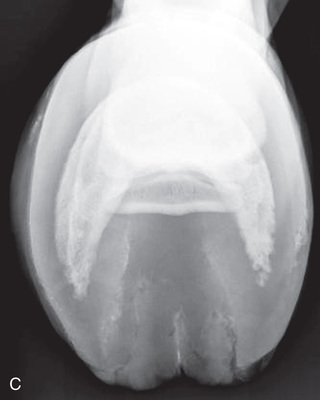

Digit/foot: P-III (distal phalanx, coffin bone) P-II (middle phalanx) P-I (proximal phalanx-pastern) Proximal interphalangeal joint (pastern joint) joint | DP (Standard) (Fig. 24.62B,C) | Dorsal 45-degree proximal–palmarodistal (D45Pr-PaDi) | Foot slightly forward on image receptor. | Perpendicular to foot axis at MSP (midsagittal plane) at area of interest with beam angled ~45 degrees to ground |

| Lateral (Standard) (Fig. 24.62D) | Lateromedial | On a block to elevate limb for P-III; resting on ground for other views. | 90 degrees lateral to MSP, parallel to ground on area of interest: coronary band for PIII | |